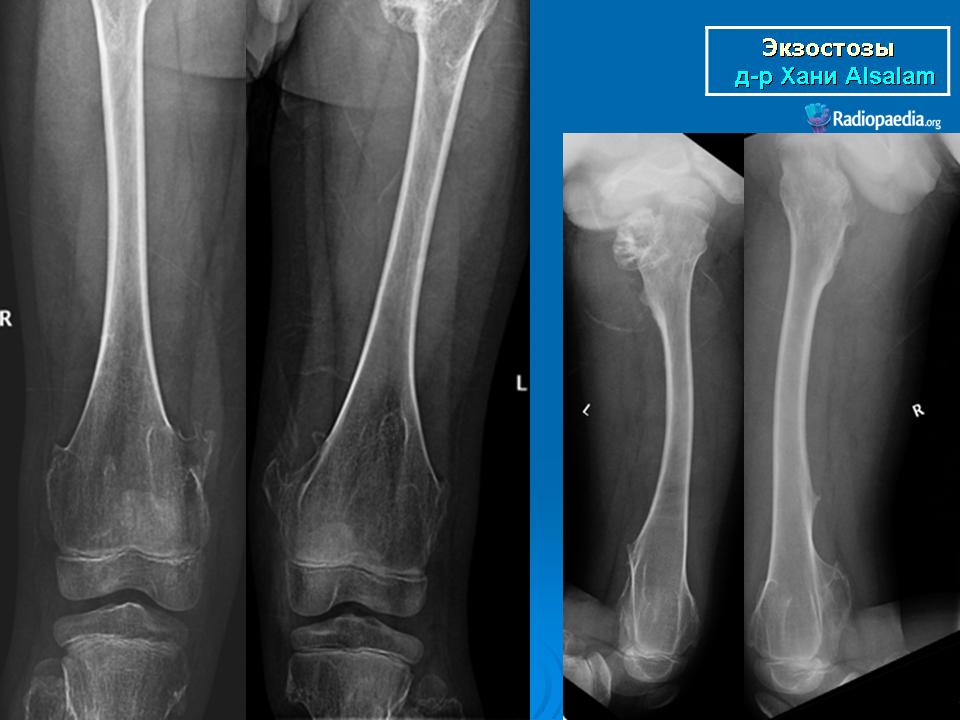

Локализация остеохондромы: частота поражения отдельных костей различна; нижний коней бедренной кости, верхние отделы плечевой и большеберцовой костей поражаются более чем у половины больных. На всем протяжении остеохондрома покрыта надкостницей. Она может быть обнаружена и в других костях, за исключением костей лицевого черепа. Все же поражение костей позвоночника, кистей рук и стоп встречается редко. При рентгенологическом исследовании видна типичная картина узкого или широкого выроста вблизи эпифизарной части пораженной кости. Обычно плотность узла неоднородная, имеются многочисленные плотные участки, соответствующие обызвествленным хрящевым долькам. Хрящевая «шапочка» большей частью не определяется, поскольку хрящ остается необызвествленным. Она может быть выявлена только при магнитно-резонансной томографии.